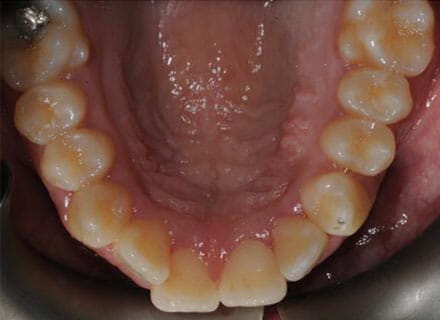

This patient came to us because she hated her smile: it was too narrow, the upper front teeth were all crowded into each other and twisted. She couldn’t eat a sandwich properly with the front teeth because of the gap – the open bite. We were able to expand both jaws to make space to align all the teeth without having to extract – in about 18 months using clear brackets.